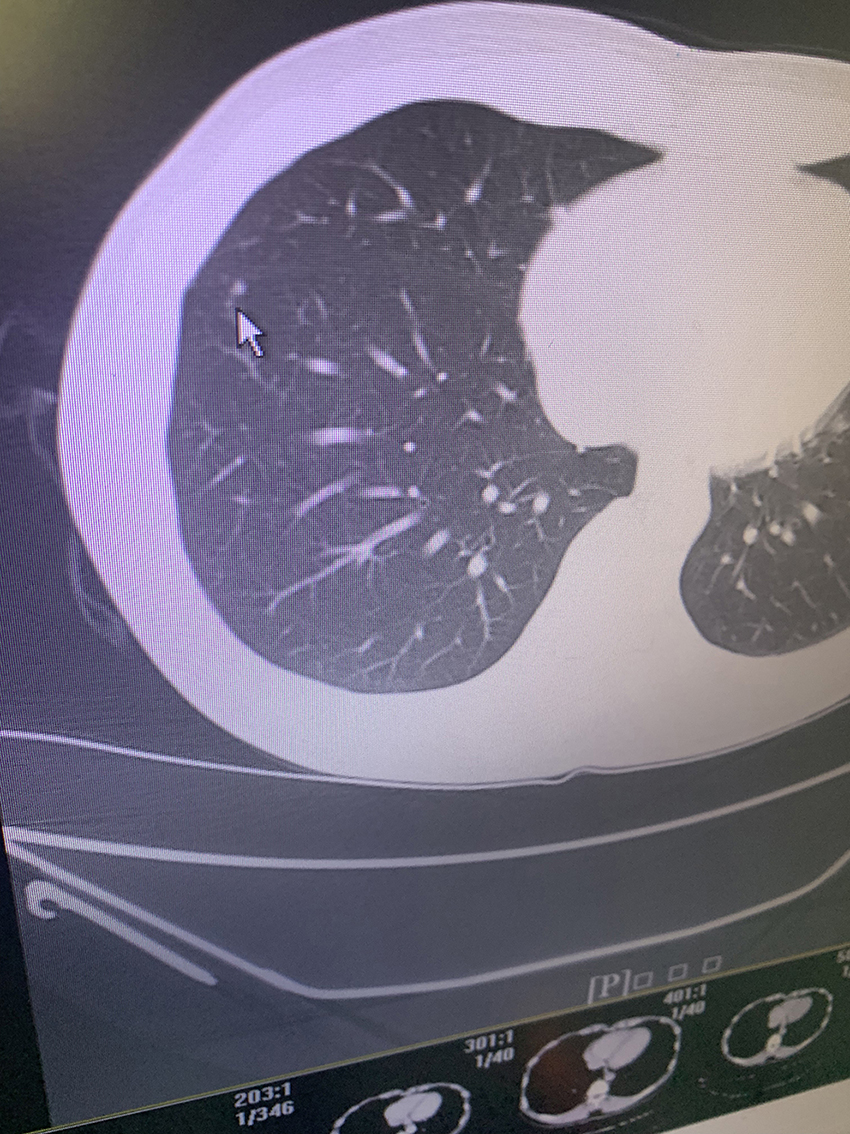

您好戴主任,我10天前体检发现肺数枚小结节,报告上只右肺有,医生看了说左右肺都有让三个月CT复查,报告也没说是实性结节还是磨玻璃,只写边界清,大的直径4MM。我39岁抽烟15年,戒有4年了,这几天心里特紧张,一直想这个事,吃不好,睡不好。在医生电脑上拍了几张照片麻烦戴主任帮看看,感谢!@重庆戴纪刚

实性微结节,良性的,偶尔复查